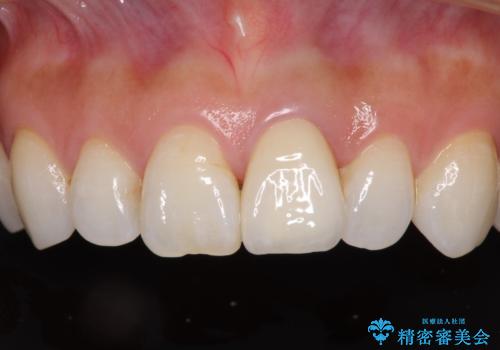

変色とともに、捻れていたことも気になっていたので、その両方を解決させることとしました。

オーダーメイドタイプのクラウンを選択いただいたので、まるで天然の歯と見間違うほど自然に仕上がり、患者様には大変満足していただきました。